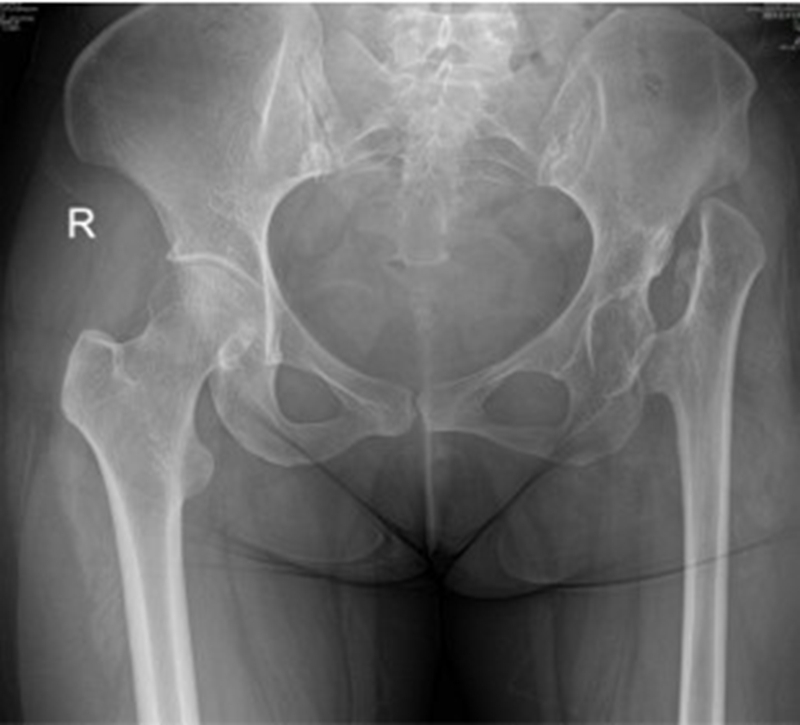

Ⅱ、股骨颈畸形---髋内外翻,offset异常

(1)颈干角偏小(<120°)——髋内翻

髋内翻,颈干角小,偏心距较大,选择high-Offset假体,以维持外展肌张力。

(2)颈干角过大(>140°) ——髋外翻

髋外翻多见于DDH,难度在于股骨距内侧皮质阻挡假体完全坐入髓腔,强行打击造成股骨距骨折。